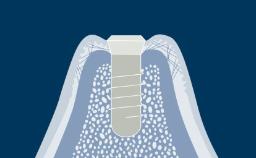

Following tooth extraction, a well-described process of wound healing takes place in the extraction socket.

A series of physiological events occur, resulting in wound healing and bone regeneration within the socket. Bone resorption results in external changes to the alveolar ridge.

The outcome of this resorption is most often a significant modification of the pre-extraction outline of the alveolar ridge, which may present a problem for later prosthetic reconstruction.

This module will present anatomic characteristics of the alveolar bone and extraction socket and will describe the histologic and dimensional changes following tooth extraction.